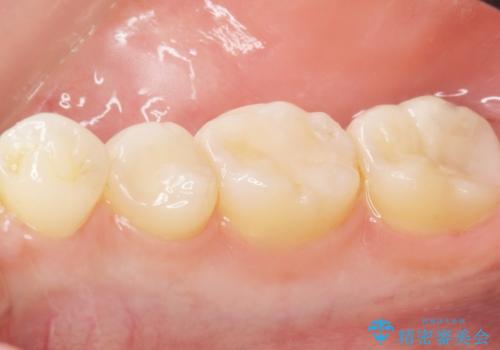

- 奥歯にフロスを通すとにおいがすることを気にされ、来院された患者様です。

精査したところ、奥歯に充填された保険内のコンポジットレジンの適合が悪いことにより、汚れがたまりやすい状態でした。

不適合なレジンを除去し、セラミックインレーによる治療を行いました。(右上76左上67右下7の計5本)

インレーの種類:セラミックインレー e-max press